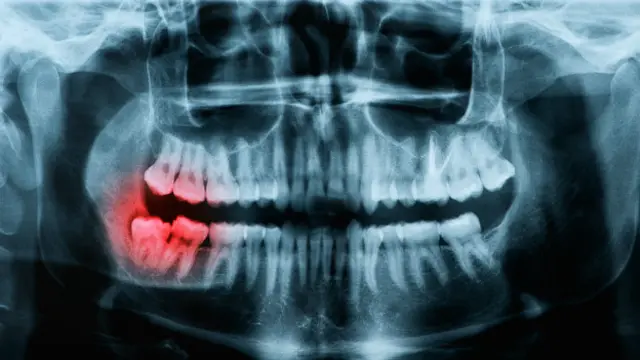

La principal razón del sangrado es la acumulación de placa, que puede causar una enfermedad conocida como gingivitis, o inflamación de las encías, que agravada puede provocar la caída de los dientes y, en casos extremos, otras complicaciones más graves.

Las encías normales son rosadas y firmes. Si sangran con facilidad, se oscurecen y/o se hinchan es importante consultar a un especialista.

Si no se trata la gingivitis se puede desarrollar una afección llamada periodontitis, que irrita las encías lo cual puede provocar más sangrado, dolor e hinchazón.

La periodontitis afecta a los tejidos que aguantan los dientes y los mantienen en su sitio.

Pero mal cuidada puede llegar a tener consecuencias más graves que la caída de los dientes.